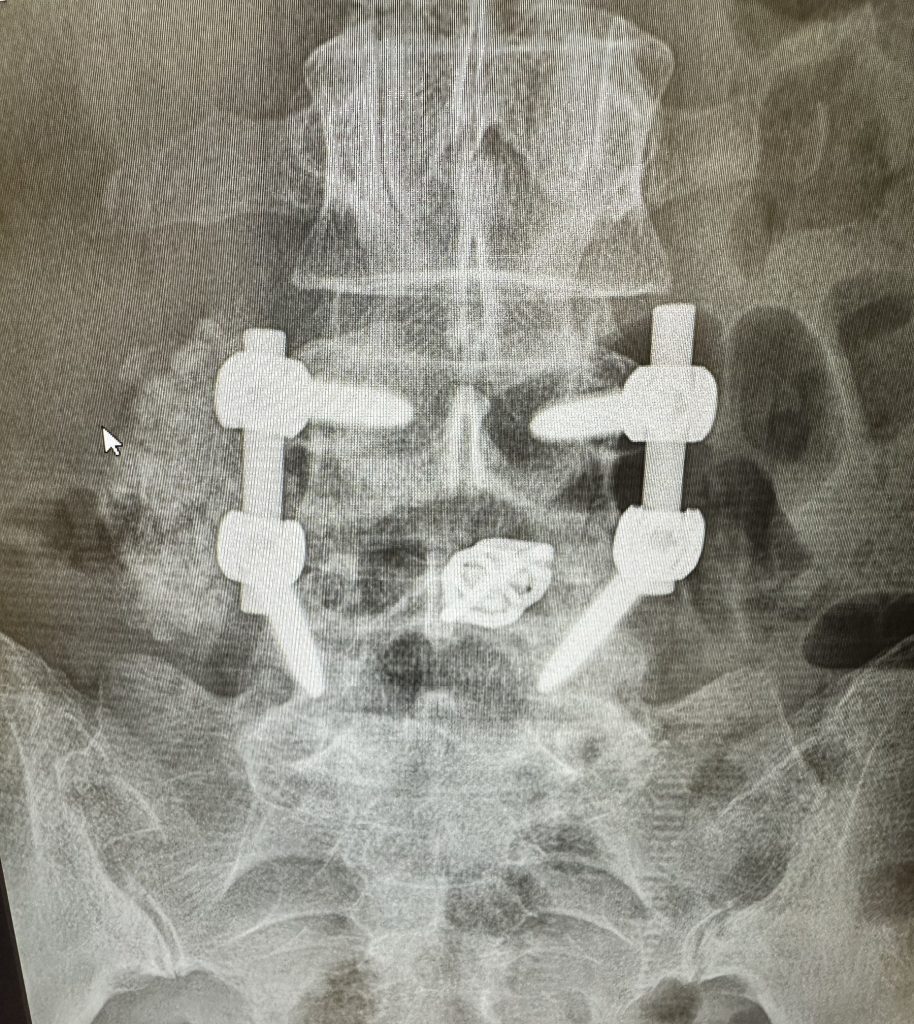

Spinal Fusion Surgery

One year and 16 days post-spinal fusion, I crossed the finish line of my first HYROX race - and I’m still trying to wrap my head around it. For those who don’t know, HYROX is a fitness competition that combines endurance running with functional strength workouts - think 8 x 1K runs with brutal stations in between. It’s no joke.

Before surgery, I could barely walk without pain. I had lost almost all use of my left leg because of severe nerve compression. The idea of competing in something like this felt impossible, but here we are.

Thank you, Dr. Han Jo Kim, for giving me my leg (and my life) back. The human body is wild - it breaks, it heals, and it can come back stronger. But it doesn’t do it alone.